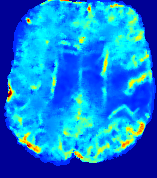

4.3.2 Diffusion Imaging via Advection-Diffusion

Slice #1Slice #2Slice #3Slice #4Slice #5Slice #6Dgtsuperscript𝐷gtD^{\text{gt}}Refer to captionRefer to captionRefer to captionRefer to captionRefer to captionRefer to captionDestsuperscript𝐷estD^{\text{est}}Refer to captionRefer to captionRefer to captionRefer to captionRefer to captionRefer to captionRefer to caption0.300.300.300.240.240.240.180.180.180.120.120.120.060.060.060.000.000.00(mm2/s)𝑚superscript𝑚2𝑠(mm^{2}/s)𝐕est𝟐subscriptnormsuperscript𝐕est2\|\bf{V}^{\text{est}}\|_{2}Refer to captionRefer to captionRefer to captionRefer to captionRefer to captionRefer to captionRefer to caption0.00300.00300.00300.00240.00240.00240.00180.00180.00180.00120.00120.00120.00060.00060.00060.00000.00000.0000(mm/s)𝑚𝑚𝑠(mm/s)

Figure 15: PIANO identifiability testing: diffusion imaging via advection-diffusion. Top row shows Dgtsuperscript𝐷gtD^{\text{gt}} used for simulating ground truth pure diffusion. Rows below show the estimated Destsuperscript𝐷estD^{\text{est}} and 𝐕est2subscriptnormsuperscript𝐕est2\|{\bf{V}}^{\text{est}}\|_{2} on corresponding slices. Note that the plotted value scale for 𝐕est2subscriptnormsuperscript𝐕est2\|{\bf{V}}^{\text{est}}\|_{2} is 0.01 of that for Dgtsuperscript𝐷gtD^{\text{gt}} and Destsuperscript𝐷estD^{\text{est}}.

Similarly, we test the behavior of PIANO when estimating both advection and diffusion from a pure diffusion-driven process. The goal is to determine if PIANO is able to recognize that there is only diffusion governing the given concentration time-series. We use the same ‘Diffusion Imaging’ data simulation of Sec. 4.2.1 as the concentration dataset, PIANO estimates both velocity 𝐕estsuperscript𝐕est{\bf{V}}^{\text{est}} and diffusivity Destsuperscript𝐷estD^{\text{est}}. Estimation results in Fig. 15 confirm PIANO’s identifiability again: the estimated 𝐕est2subscriptnormsuperscript𝐕est2\|{\bf{V}}^{\text{est}}\|_{2} is almost invisible compared to Destsuperscript𝐷estD^{\text{est}}, even plotted with a 1%percent11\% value range compared to that for Destsuperscript𝐷estD^{\text{est}}. On the other hand, Destsuperscript𝐷estD^{\text{est}} achieves comparable estimation performance as ‘Diffusion Imaging via Diffusion’ in which PIANO predicts Destsuperscript𝐷estD^{\text{est}} alone (shown in Fig. 13).